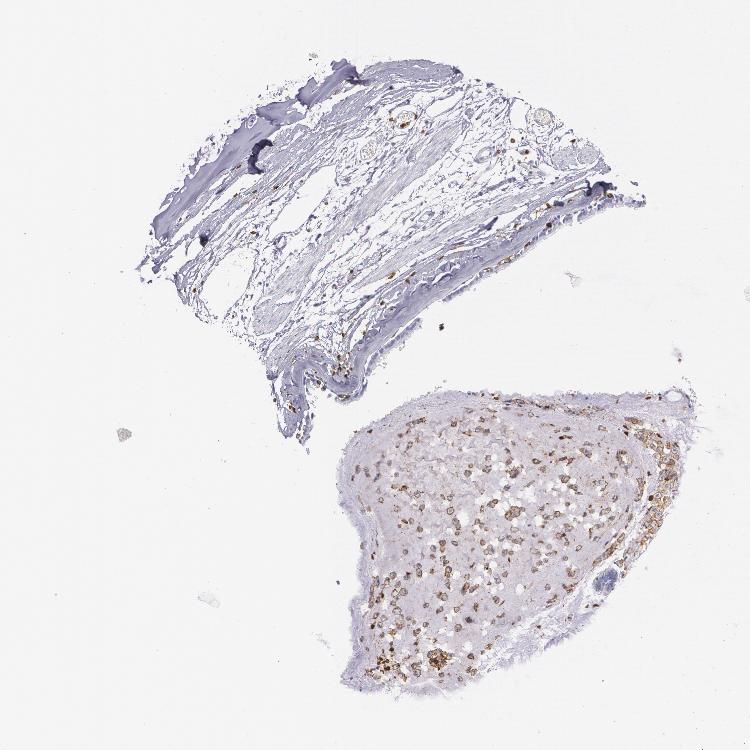

SOFT TISSUE 1 - Antibody stainingi

Antibody staining in the annotated cell types in the current human tissue is reported as not detected, low, medium, or high, based on conventional immunohistochemistry profiling in selected tissues. This score is based on the combination of the staining intensity and fraction of stained cells.

Each image is clickable and will lead to virtual microscopy that enables deeper exploration of all samples and also displays staining intensity scores, fraction scores and subcellular localization as well as patient and tissue information for each sample.

Antibody HPA000440Antibody CAB000052Antibody CAB002800Antibody CAB056154Antibody CAB068221Antibody CAB080251

Chondrocytes Not detected---Not detectedNot detected

Fibroblasts Not detectedNot detectedNot detectedNot detectedMediumNot detected

Peripheral nerve --Not detected---